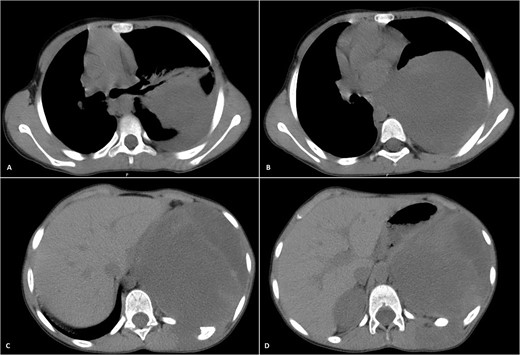

Physical examination unveiled a painless, solid mass characterized by hardness, emerging from the left lower chest and measuring 13 × 15 × 2 cm. This mass exhibited adherence to its surroundings, with no apparent pathological vasculature (Fig. 1). After this examination, a chest CT was conducted, revealing a huge, well-defined, and heterogeneous mass lesion occupying the left lower hemi-thorax. This imposing mass resulted in a noticeable reduction in left lung volume and a significant rightward mediastinal shift, measuring ~13.4 × 15.9 × 12.3 cm (Figs 2 and 3).

Selected axial CT images with mediastinal windowing showing multiple cuts of the patient’s chest. A huge relatively well-defined heterogeneous mass lesion is noted occupying the left lower hemi-thorax causing left lung volume loss and significant rightward mediastinal shift. No definite invasion of the adjacent ribs, however, remodeling of the lower aspect of the left posterior tenth rib is noted with the widening of the left tenth intercostal space and involvement of the left erector spinae muscles by the previously mentioned mass.